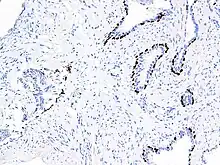

Diagnostic utility

p63 immunostaining has utility for head and neck squamous cell carcinomas, differentiating prostatic adenocarcinoma (the most common type of prostate cancer) and benign prostatic tissue;[23] the nuclei of the basal cells of normal prostatic glands stain with p63, while the malignant glands in prostatic adenocarcinoma (which lacks these cells) do not.[24] P63 is also helpful in distinguishing poorly differentiated squamous cell carcinoma from small cell carcinoma or adenocarcinoma. P63 should be strongly stained in poorly differentiated squamous cell, but negative in small cell or adenocarcinoma.[25]

Cytoplasmic staining on immunohistochemistry is seen in cells with muscle differentiation.[26]